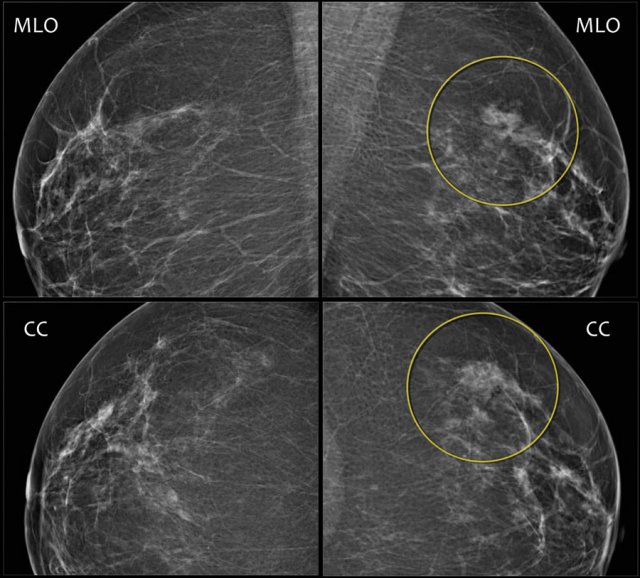

Here an example of a focal asymmetry seen on MLO and CC-view.

Local compression views and ultrasound did not show any mass.